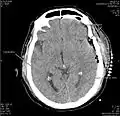

بطن چهارم یکی از بطنهای مغزی است که همانند بطنهای طرفی و بطن سوم حاوی مایع مغزی-نخاعی بوده که این مایع توسط شبکه کوروئیدی هر یک از بطنها ترشح میگردد. این بطن لوزی شکل بوده که در مغز خلفی قرار دارد. بطن چهارم از طریق یک سوراخ ماژندی و دو سوراخ لوشکا، با فضای زیر عنکبوتیه ارتباط دارد. بیشتر مایع مغزی-نخاعی از این سوراخها به فضای زیر عنکبوتیه منتقل میشود، ولی مقدار کمتری از مایع مغزی-نخاعی به مجرای اپاندیم (مجرای مرکزی طناب نخاعی) جریان مییابد. انسداد در بطنهای مغزی باعث تجمع مایع مغزی-نخاعی در بطنها میگردد که نتیجه آن هیدروسفالی است.

جریان مایع مغزی-نخاعی از بطنهای طرفی به بطن سوم و سپس بطن چهارم است. بطن طرفی از طریق مجرای مونرو با بطن سوم ارتباط دارد. مایع مغزی-نخاعی از مجرای سیلویوس (مجرای مغزی) به بطن چهارم انتقال مییابد. در نهایت این مایع بوسیله سه سوراخ بطن چهارم (دو سوراخ لوشکا و یک سوراخ ماژندی) که در سقف بطن چهارم قرار دارند به فضای زیر عنکبوتیه در تمام قسمتهای دستگاه عصبی مرکزی میرود.